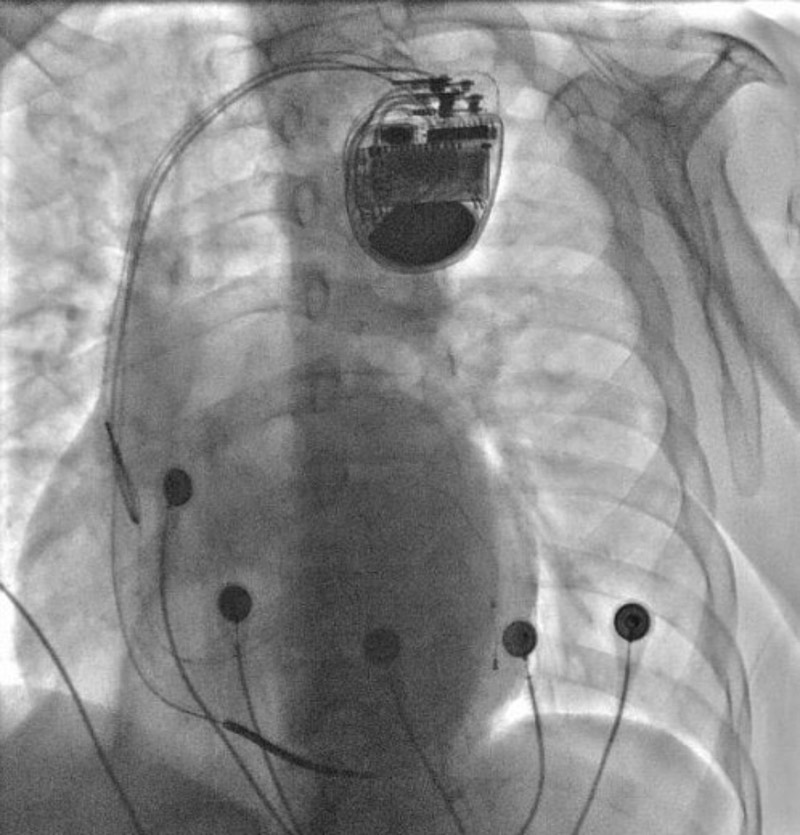

心血管內科電生理團隊經過術前詳細的手術方案討論和制定,術中精準操作,成功完成了心臟再同步化除顫起搏器CRT-D植入術。術后復查心電圖示QRS波恢復到119ms,明顯變窄,患者心臟功能及癥狀較手術前顯著改善。